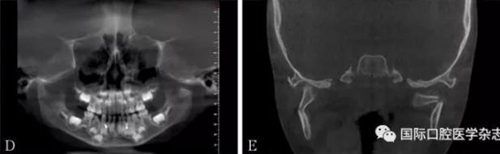

左:顴弓骨折CT平掃;右:顴弓骨折CT三維成像。

圖 10 顴弓骨折